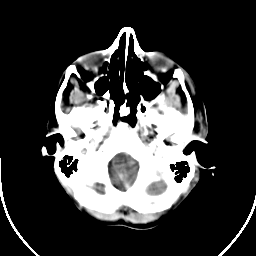

Metastatic bronchogenic carcinoma: Roentgen-ray CT (post-op) -- Slice #2

[Home][Help][Clinical] Slice 2